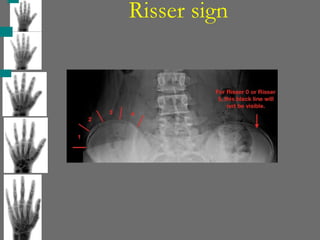

Risser sign

Risser sign is a radiological tool used to assess scoliosis. It is based on

the degree of ossification and fusion of the iliac crest apophysis. This

information helps predict the risk of scoliosis progression during a

patient’s growth phase.

Grading of the Risser Sign

 Grade 0: No ossification of the iliac apophysis. Indicates early

skeletal growth and maximum potential for scoliosis progression.

 Grade 1: Ossification of the apophysis begins, covering up to 25% of

the iliac crest.

 Grade 2: Ossification progresses to cover 26–50% of the iliac crest.

 Grade 3: Ossification extends over 51–75% of the iliac crest.

 Grade 4: Ossification is nearly complete, covering 76–100% of the

iliac crest, but the apophysis is not yet fused to the iliac crest.

 Grade 5: Complete fusion of the apophysis to the iliac crest,

signaling skeletal maturity

Clinical Importance:

The Risser sign is a key component in scoliosis

management, as it helps predict growth potential and the

risk of curve progression.

 Low Risser grades (0–2): Indicate active growth phases

with a higher risk of scoliosis progression.

 High Risser grades (3–5): Suggest reduced growth

potential and a lower risk of scoliosis worsening.

Limitations:

 Differences in Risser grading systems exist between the

U.S. and Europe, with slight variations in interpretation.

 Other methods like the Tanner staging and hand-wrist

radiographs may also be used for growth assessment in

conjunction with the Risser sign.